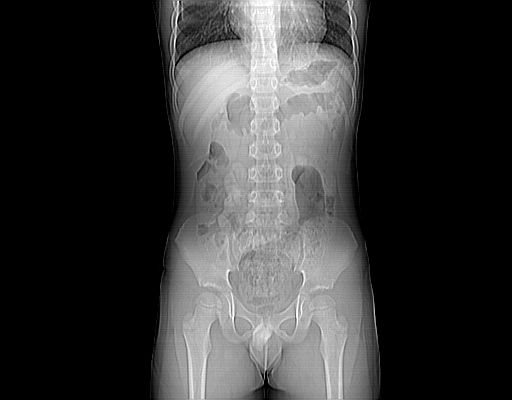

标题: PED3104:男,7岁,反复腹痛3年,再发2天。WBC:10.8X10 9/L,粪 [打印本页]

标题: PED3104:男,7岁,反复腹痛3年,再发2天。WBC:10.8X10 9/L,粪

腹部好象未见异常。

腹部ct平扫未见明确异常

腹部ct平扫不能提示哪里有病变。